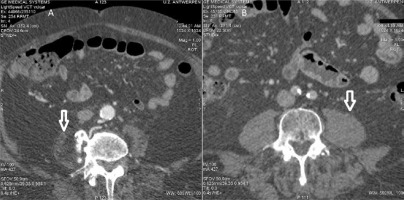

FIGURE 1

Panel A shows an example of a patient suffering from sarcopenia. Panel B shows an image of a non-sarcopenic patient. Note the difference in psoas muscle volume. Note the difference in psoas muscle cross-sectional area (white arrow) between the two patients